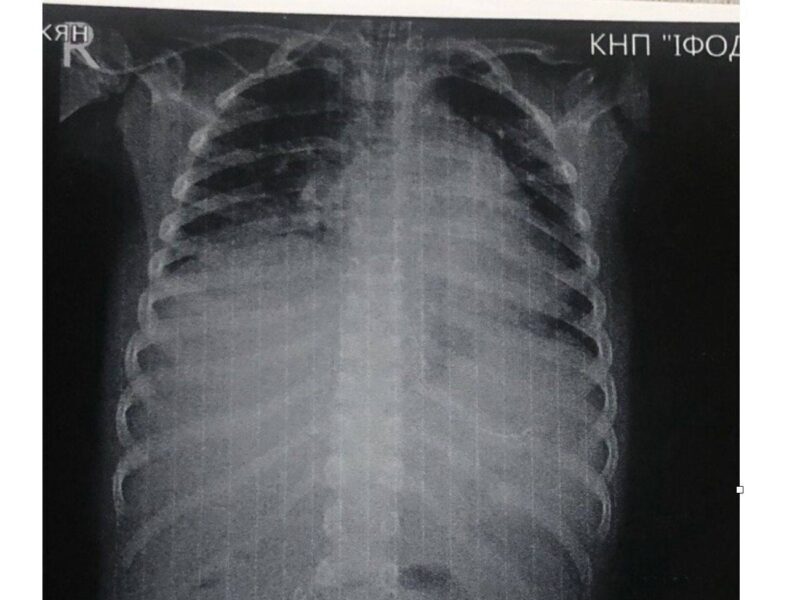

До Івано-Франківської обласної дитячої клінічної лікарні привезли 7-річного хлопчика в стані інфекційно-токсичного шоку з ознаками розлитого перитоніту. Як з’ясували лікарі, причиною стало проковтування батарейки, яка спричинила перфорацію тонкого кишківника.

Підготовка до операції тривала 12 годин. Загалом медики провели три оперативні втручання.